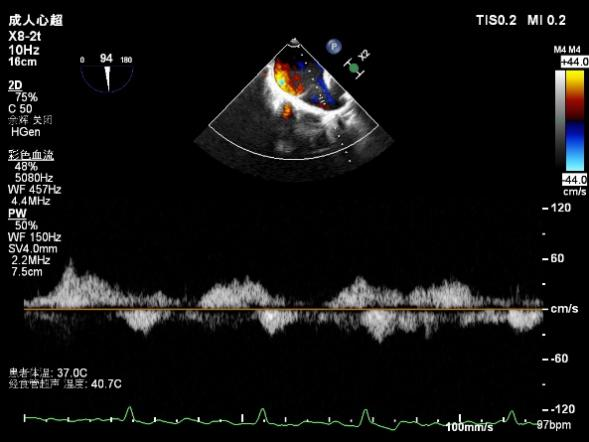

肺静脉血流频谱恢复正向

二尖瓣瓣口平均跨瓣压差:3mmHg